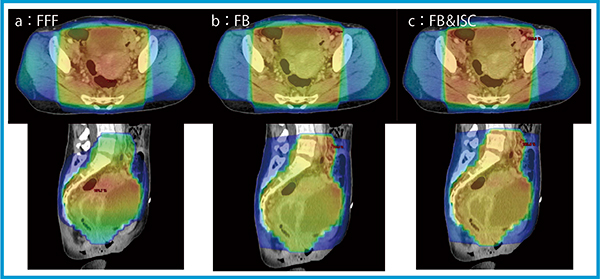

1.子宮頸がんの治療計画

子宮頸がんの4門照射において,FFFビームでは照射中心部に高線量部が発生してしまうため臨床的に不適切である。FBを使用すると腫瘍部へ均一な照射が可能となるが,max doseが113.7 %と高いケースがある。このような場合は,さらにガントリ90°と270°にISCを追加することで,均一な分布の作成が可能である(図3)。

図3 Halcyonによる子宮頸がんの線量分布

a:FFF max:103.5%,min:69.1%,mean:91.4%,monitor unit(MU):38.6/ 44.6/59.0/56.5

b:FB max:113.7%,min:90.4%,mean:101.2%,MU:92.7 /108.2/142.1/136.2

c:FB & ISC max:109.6%,min:90.3%,mean:100.5%,MU:129.1 /138.6/ 95.6/114.1